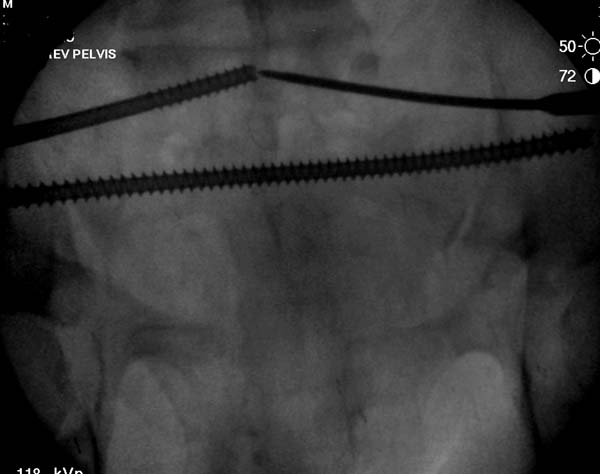

Вход в таз

На картинке, для репозиции свежих разрывов в КПС мы применяем такой способ. За скобу через блок. Груз достаточно большой. Перед этим опускаем головной конец в качестве противотяги, т.к. промежностный упор не используем. Обычно тяги хватает. Попробуйте.

Большое спасибо всем Вам за помощь! Вчера прооперировали пациентку. Выполнили закрытую репозицию левой половины таза на тракционном столе под контролем ЭОП, закрытая фиксация левого КПС двумя каннулированными винтами. Учитывая удовлетворительное стояние отломков лонной и седалищной костей справа, а так же удовлетворительную ширину лона передние отделы стабилизировали системой ЦИТО

Винты введены в S1